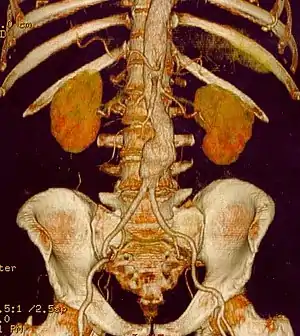

Abdominal aortic aneurysm

Abdominal aortic aneurysms (AAAs) are more common than their thoracic counterpart. One reason for this is that elastin, the principal load-bearing protein present in the wall of the aorta, is reduced in the abdominal aorta as compared to the thoracic aorta. Another is that the abdominal aorta does not possess vasa vasorum, the nutrient-supplying blood vessels within the wall of the aorta. Most AAA are true aneurysms that involve all three layers (tunica intima, tunica media and tunica adventitia). The prevalence of AAAs increases with age, with an average age of 65–70 at the time of diagnosis. AAAs have been attributed to atherosclerosis, though other factors are involved in their formation.

The risk of rupture of an AAA is related to its diameter; once the aneurysm reaches about 5 cm, the yearly risk of rupture may exceed the risks of surgical repair for an average-risk patient. Rupture risk is also related to shape; so-called "fusiform" (long) aneurysms are considered less rupture prone than "saccular" (shorter, bulbous) aneurysms, the latter having more wall tension in a particular location in the aneurysm wall.

Before rupture, an AAA may present as a large, pulsatile mass above the umbilicus. A bruit may be heard from the turbulent flow in the aneurysm. Unfortunately, however, rupture may be the first hint of AAA. Once an aneurysm has ruptured, it presents with classic symptoms of abdominal pain which is severe, constant, and radiating to the back.

The diagnosis of an abdominal aortic aneurysm can be confirmed at the bedside by the use of ultrasound. Rupture may be indicated by the presence of free fluid in the abdomen. A contrast-enhanced abdominal CT scan is the best test to diagnose an AAA and guide treatment options.